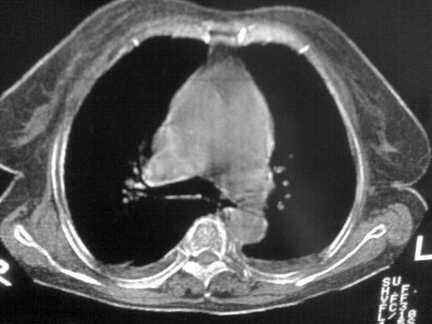

标题: CT13142:女 80 胸闷、气短、1w [打印本页]

标题: CT13142:女 80 胸闷、气短、1w

右肺炎性变,双侧甲状腺肿,胸膜肥厚。

右肺炎性变

双侧胸腔积液

缩窄性心包炎

左室为主的心脏增大。

胸膜肥厚,

气管,支气管软骨钙化。

右肺感染;双侧胸腔少量积液,心影增大,可能与心功不全有关;胸内甲状腺肿。

右肺炎性变,双侧甲状腺肿,胸膜肥厚,心影增大考虑心功能不全.

胸内甲状腺肿;右肺感染;双侧胸腔少量积液。

胸内甲状腺肿;右肺中叶感染;双侧胸腔少量积液;心影增大,考虑有心功能不全。